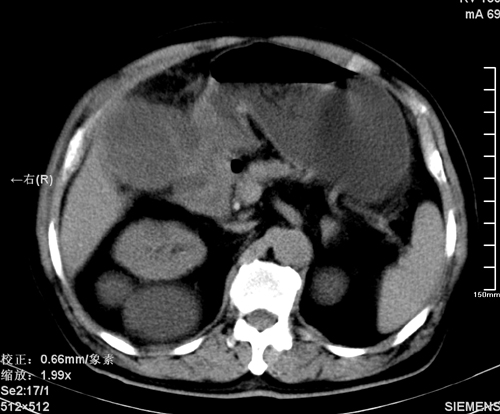

以下是引用liaoqiang在2008-3-27 15:57:00的发言:[br]1右肾脏周多发大小不一球形影,考虑肾脏囊肿可能性大。2胆囊边界欠清楚。考虑胆囊炎可能性。

以下是引用随光逐影在2008-3-27 16:33:00的发言:[br]考虑为:1)双肾囊肿可能。2)急性胆囊炎。建议:行进一步检查。